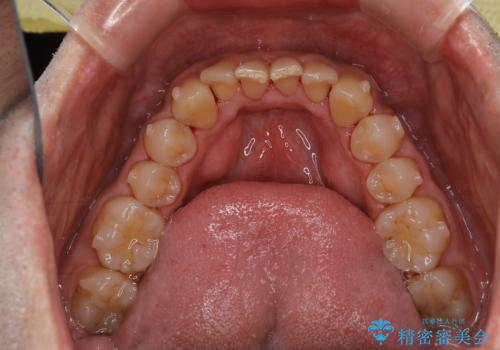

- インビザラインの治療中ですが、歯石やステインが気になるとのことでした。

コーヒーが大好きでよく飲むそうです。

全体的に歯石やステインが付着していたため、エアフロー60分コースを行いました。